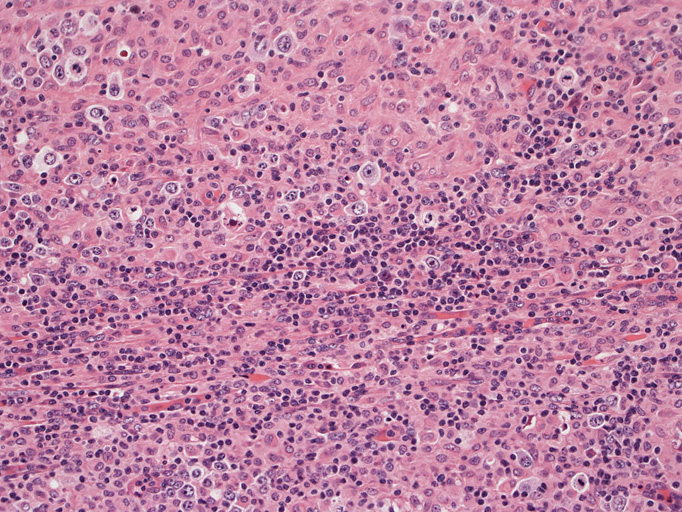

直径17mmの腫大したリンパ節。被膜は軽度線維性肥厚を示す。リンパ節の基本構造は失われ不明瞭な結節様構造が集蔟しているように見える。

結節構造内では, 好酸性細胞質をもつ組織球の増生を背景に大型異型細胞が散在性または集蔟して増殖している。被膜下にも線維化組織内にbizzarreな大型細胞が認められる。リンパ球は小型リンパ球が大型異型細胞を含む組織球性の結節辺縁に存在する。大型細胞は, centroblastic cellが多く, その他 Hodgkin cell-like cell, RS細胞様巨細胞, 腎臓型の核をもった細胞, 多型核の細胞など多彩な形態を示す。異型核分裂像をふくむ核分裂像が多い。

大型異型細胞の形態